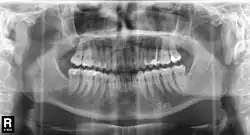

En novembre 1895, Wilhelm Röntgen découvre les rayons X, qui simplifient l'exploration de la mâchoire. En 1905, l'anesthésique local procaïne est mis au point par les chimistes allemands Alfred Einhorn et Emil Uhlfelder, qui lui attribuent le nom de Novocaïne (néologisme latin pour nouvelle cocaïne). C'est ainsi que les bases sont posées pour le diagnostic et la thérapeutique modernes. La dentisterie subit alors des progrès rapides : depuis la mise au point de nombreux procédés de chirurgie dentaire jusqu'à la confection de prothèses dentaires par CFAO. Parallèlement aux progrès de la dentisterie scientifique, le tableau de la profession s'organise. Par ailleurs, il se développe une médecine dentaire vétérinaire, qui se sert des procédés de la médecine dentaire générale convenablement adaptés.

Le 23 janvier 1896, Wilhelm Röntgen présente à la société de physique médicale les rayons qu'il a nommés rayons X, qu'il a découverts en novembre 1895. C'est alors la main de l'anatomiste et physiologiste Albert von Kölliker qui sert d'objet pour la présentation. Après la présentation, Kölliker propose la dénomination de rayons Röntgen, alors que Röntgen les avait appelés jusqu'alors rayons X. Les deux désignations perdurent selon les aires linguistiques[126]. En janvier 1896 le dentiste Otto Walkhoff, dont Röntgen était patient, aurait fait les premières radiographies de dents, avec un temps de pose de 25 min[32]. L'utilisation de rayons X pour le diagnostic en médecine dentaire a été rendu possible par le travail de Charles Edmund Kells, un dentiste de la Nouvelle-Orléans, qui l'a présenté en juillet 1896 devant des dentistes à Asheville[127].

Antoni Cieszyński (1882−1941), médecin, dentiste et chirurgien polonais, considéré comme fondateur de la médecine dentaire polonaise, a mis au point la technique isométrique : pour minimiser les distorsions dans la radiographie d'une dent, il faut que les rayons soient perpendiculaires au plan bissecteur entre l'axe de la dent et le plan du film[128].

En 1934, le Japonais Hisatugu Numata met au point le premier appareil à panoramiques X dentaires. La mise au point de l'appareil intraoral, où le tube émetteur se trouve à l'intérieur de la bouche et le film à l'extérieur suit. En parallèle, Horst Beger, de Dresde, en 1943 et Walter Ott, dentiste suisse, en 1946 mettent au point les appareils Panoramix (Koch & Sterzel), Status X (Siemens) und Oralix (Philips)[129]. Le Finlandais Yrjö Veli Paatero (1901–1963) continue à mettre au point la technique et donne à l'appareil le nom de Parabolographie, puis de Pantomographie en 1950, et enfin sur la suggestion du Japonais Eiko Sairenji le nom Orthopantomographie en 1958[130],[131],[132]. Le premier de ces appareils est distribué en 1961 sous le nom de Panorex par la firme S.S. White[133]. Les tubes émetteurs et le film y tournent de façon synchrone autour de la tête du patient. À la fin des années 1980, les appareils panoramiques intraoraux sont abandonnés définitivement, parce que la dose de rayonnement par le tube en contact avec la langue et la muqueuse buccale se trouve trop élevée.

En 1987, Trophy Radiology (France) a mis sur le marché le premier appareil à rayons X numérique pour images dentaires intra-orales sous le nom de Radiovisiographie. En 1995, DXIS, le premier appareil panoramique dentaire numérique est introduit par Signet (France), suivi en 1997 par SIDEXIS, (Siemens, plus tard Sirona) avec Ortophos Plus. Au lieu d'un film, les appareils contiennent un scintillateur, qui transforme les photons X incidents soit en lumière visible soit directement en impulsions électriques. Les données captées dans le détecteur sont renvoyées sous forme numérique à l'écran d'un ordinateur[134].